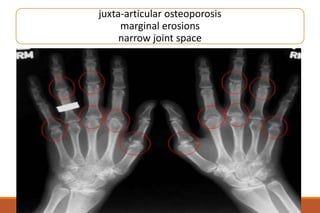

RHEUMATOID ARTHRITIS

X-rays

◦ The earliest changes occur in the wrist or feet and consist of soft

tissue swelling and juxta-articular demineralization.

◦ Later, diagnostic changes consisting of joint space narrowing and

erosions develop. The erosions are first seen at the ulnar styloid

and at the juxta-articular margin, where the bony surface is not

protected by cartilage.

Juxta-articular osteoporosis

Bony erosions

erosion

geodes

marginal erosions

narrow joint space